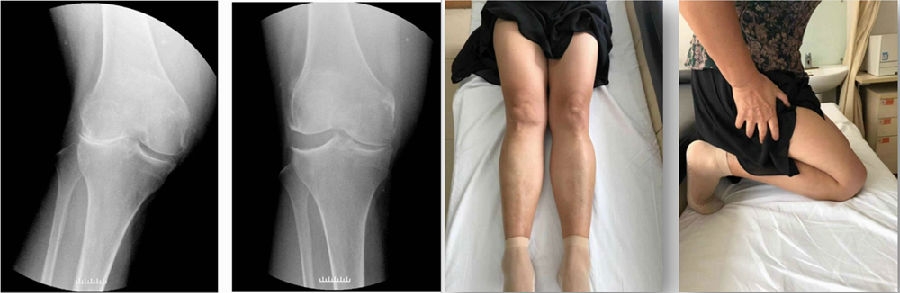

Case1:LUK治疗外侧间室OA

术前

术后